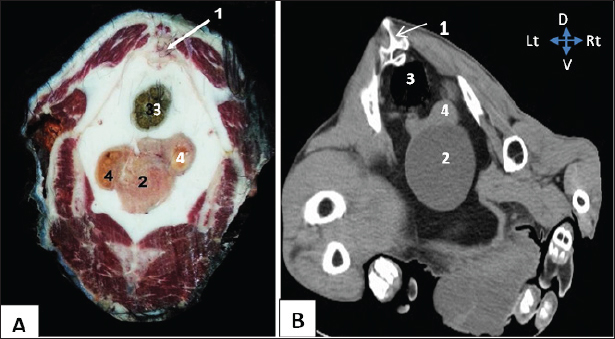

Figure 1 shows the visualization of the right kidney, located at the 12th thoracic vertebral level, specifically to the right of the median plane. The structure in question exhibited a dorsal relationship with the thoracic vertebrae, a lateral relationship with the ribs, a medical association with the dorsal ruminal sac, and an embedded location inside the renal impression of the caudate lobe of the liver.

The left solitary kidney was observed at the second lumbar vertebral level, positioned to the right of the median plane (Fig. 2). The dorsal ruminal sac, as observed in the dorsal-plane CT scan (Fig. 4), resulted in the displacement of the left kidney toward the right side of the abdomen and the caudal migration toward the right kidney. The left kidney exhibited a dorsal relationship with the lumbar spine, a medial relationship with the dorsal ruminal sac, and a ventrolateral relationship with the intervening intestine.

Fig. 3. Representative macrographic image of cross-sectional anatomy (Panel A) and computed tomography image (5-mm thickness) (Panel B) of the goat pelvis. Panel (A –B): 1- Sacrum; 2-Urinary bladder; 3- Rectum; 4-Uterus.